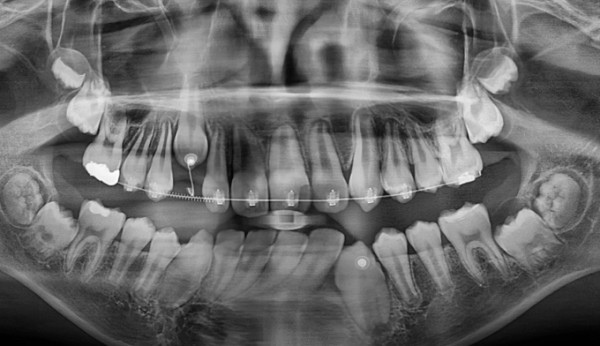

간단히 해당 위치를 절개 후 물혹을 제거해주고 치아를 제 위치로 이동시켰습니다.

총 교정기간은 13개월입니다.